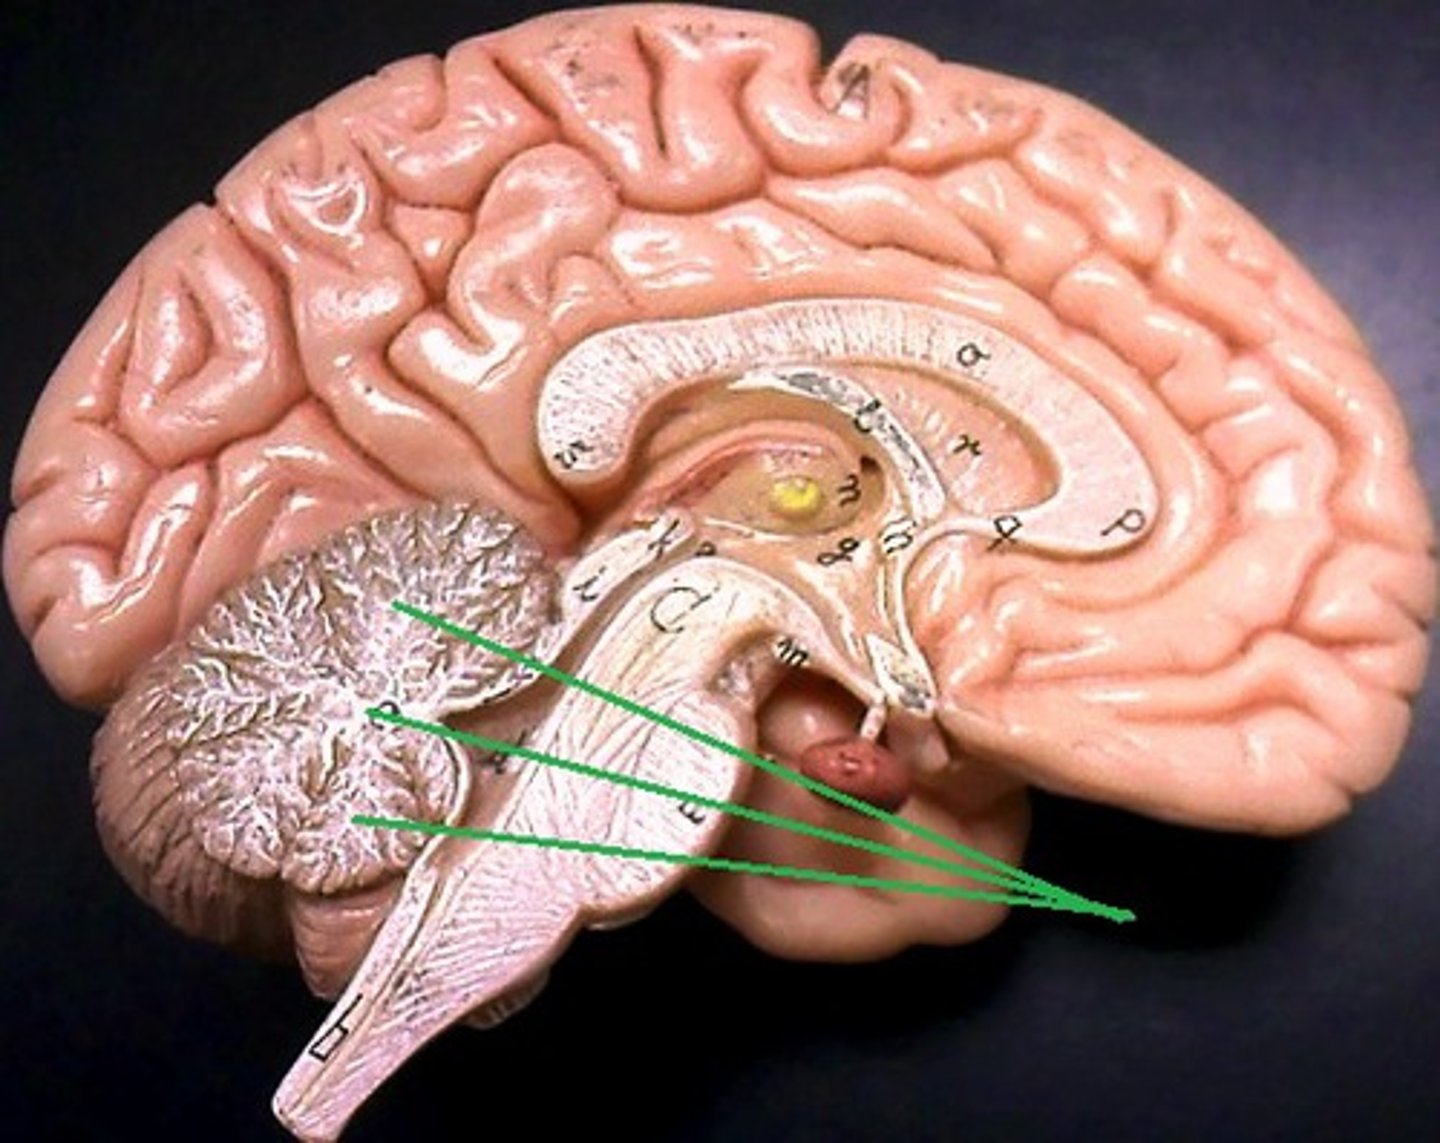

pons

cerebellum

arbor vitae

vermis

Connects the two hemispheres of the cerebellum

cerebral aquaduct

fourth ventricle

medulla oblongata

midbrain